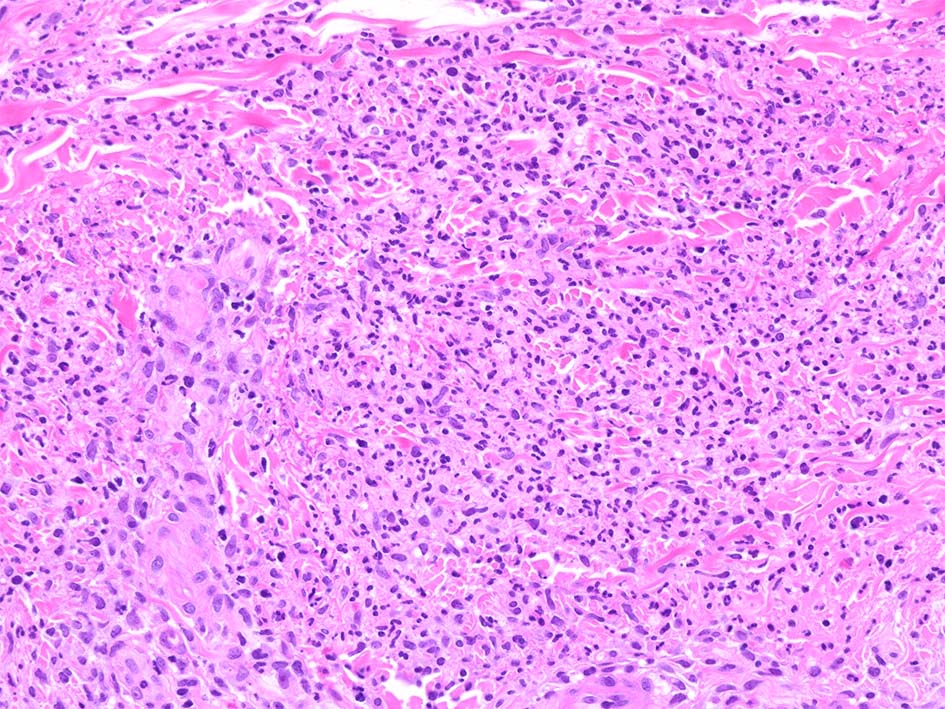

HE x40. 表皮下水疱あり. 真皮上層は浮腫状. 真皮から皮下組織にかけて, 多数の好中球が浸潤している. リンパ球, 好酸球が混在, 核破砕物を貪食するマクロファージが増加. 膠原線維にはところどころ変性が見られる.

真皮上層には核破砕物が多く, 好中球浸潤が認められる. 慢性炎症性細胞も浸潤している.

フィブリノイド壊死を呈する血管炎は認められない.

皮下脂肪織炎病変には局所的なhemophagocytosisが認められる. 血管にはfibrinoid necrosisは見られない。